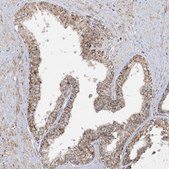

immunohistochemistry: 1:50-1:200

All Prestige Antibodies Powered by Atlas Antibodies are developed and validated by the Human Protein Atlas (HPA) project and as a result, are supported by the most extensive characterization in the industry.

The Human Protein Atlas project can be subdivided into three efforts: Human Tissue Atlas, Cancer Atlas, and Human Cell Atlas. The antibodies that have been generated in support of the Tissue and Cancer Atlas projects have been tested by immunohistochemistry against hundreds of normal and disease tissues and through the recent efforts of the Human Cell Atlas project, many have been characterized by immunofluorescence to map the human proteome not only at the tissue level but now at the subcellular level. These images and the collection of this vast data set can be viewed on the Human Protein Atlas (HPA) site by clicking on the Image Gallery link. We also provide Prestige Antibodies® protocols and other useful information.

- IHC tissue array of 44 normal human tissues and 20 of the most common cancer type tissues.